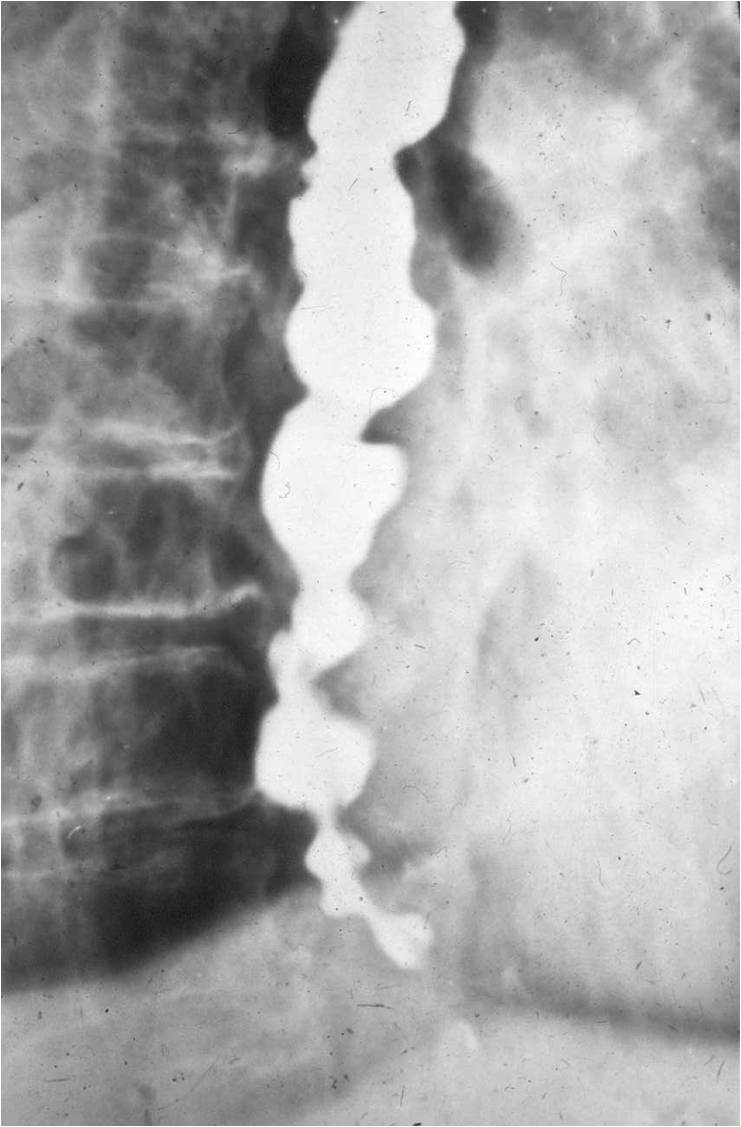

Image

Fig.3.: Pseudo-diverticulosis

Radiographic findings: rosary-bead like outpouchings of the esophagus. Static peristaltic waves are seen. These are ineffective in passing forward the esophageal contents.